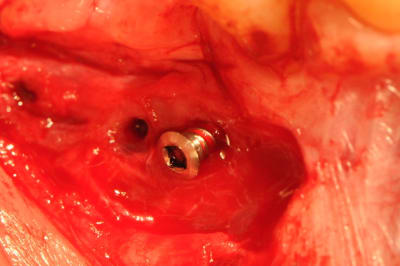

photo 6-7-8 : retrait des vis FAST ayant servi de piquet de tente à la ROG

Sur la photo vis en place : elle est déjà un peu dévissée, ou il y a eu 2 mm de perte du matériaux ? ( c'est ce que j'ai eu aussi les deux fois ou j'ai fait cette technique ).

En effet si on compare la photo de ton post initial par rapport à la photo de la réouverture, on peut voir que la vis dépasse toujours autant par rapport au niveau osseux initial.

pour clio et jeff, la photo montrant la vis est trompeuse et je comprends mieux vos réactions.

en fait elle n'était pas dans sa position initiale car j'ai fait la photo avec la vis ayant été retirée à moitié.

photos 1 et 2 mise en place des vis et comblement osseux.

photo 3 et 4 le niveau osseux n'a pratiquement pas bougé.